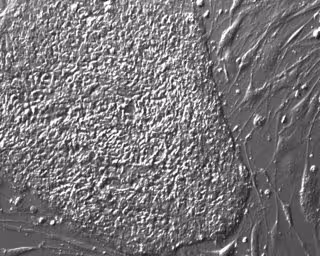

Archivo - Células madre pluripotentes humanas diseñadas.

Archivo - Células madre pluripotentes humanas diseñadas. - ALPHAMED PRESS - Archivo